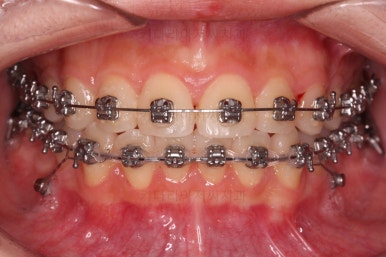

이번에 사용한 장치는 엠파워메탈이라고 하는 자가결찰(철사를 잡아주는 뚜껑이 달려있는) 메탈(금속 성분) 장치였어요.

매우 장점이 많으나 심미성과 재료제작 비용 때문에 상대적으로 저렴한(이것도 장점일 수 있죠.) 장치입니다.

장치를 부착했을 때 입이 나오는 느낌, 웃을 때 느낌은 참고해 주세요.

사랑니 발치는 별도의 스케줄로 진행되었습니다.

(부산교정 키다리아저씨치과는 사랑니를 잘 뽑으시는 원장님이 계십니다.)